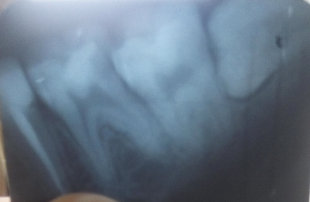

На каких зубах существует вероятность пульпита? 2. Есть ли вероятность, что на снимке присутствуют зубы, такие, что зуб значительно разрушен (от четырёх поверхностей), поэтому здесь требуется восстановление. То есть речь идёт о ситуации кариеса, когда пострадало более трёх поверхностей. Как известно, любой зуб имеет пять поверхностей (1. С внешней стороны. 2. С внутренней стороны (со стороны языка). 3. Со стороны левого соседнего зуба. 4. Со стороны правого соседнего зуба. 5. С жевательной стороны. Я понимаю, что точно диагноз нельзя поставить только по снимку, потому что нужен и визуальный осмотр, но речь идёт просто о возможности (подозрительных зубах и наиболее сложных).

Прям четких пульпитных явлений на снимке я не увидел. Шестой зуб сверху (26), требует установки коронки из-за большого количества пломбы, что по показаниям требуется реставрация вкладкой и коронкой. Не знаю про какой зуб идёт речь, но при разрушении коронковой части зуба более, чем на 50%, необходимо устанавливать коронки. Для более подробной консультации, обратитесь к стоматологу на очный приём.